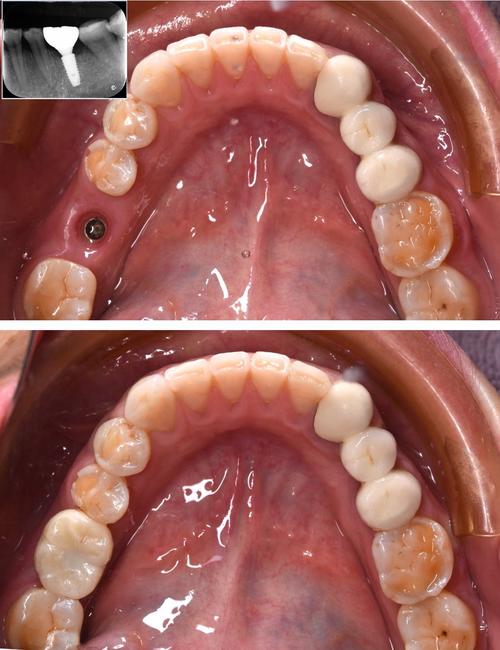

(图片来源网络,侵删)- 种植牙前通常需要拍摄口腔X光片(根尖片、曲面断层片)或CBCT(锥形束CT)来评估骨量,虽然CBCT的辐射剂量远低于医疗CT,且铅衣防护可以大大减少腹部暴露,但原则上应避免在孕期进行不必要的电离辐射检查,如果必须拍片,应严格使用铅衣防护腹部,并尽可能选择辐射剂量最低的检查方式(如根尖片替代CBCT)。